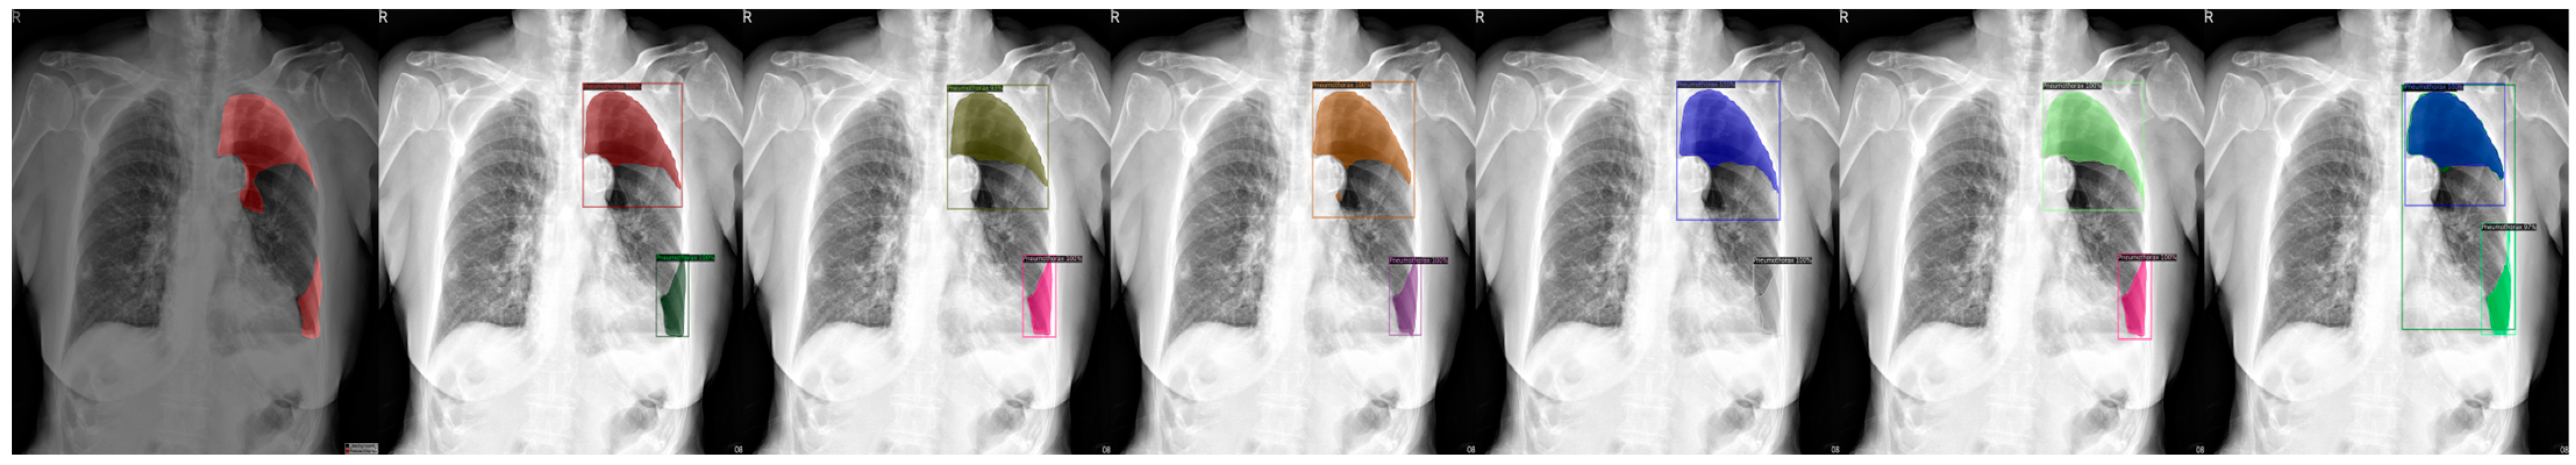

Figure 6.

From left to right: Ground Truth, ResNet50 (COCO), ResNet101 (COCO), ResNeXt101 (COCO), ResNet50 (LVIS), ResNet101 (LVIS), and ResNeXt101 (LVIS). This patient had pneumothorax in their right chest.

We chose a few examples to demonstrate the capabilities of various models. These images consisted of X-ray images of pneumothorax patients with different areas of disease inflicted. The inclusion of multiple positions and areas in the figures lets us observe the possible outcomes and the differences between the models. In Figure 3 and Figure 6, the patients had pneumothorax on the right side of their chest, with the patient in Figure 6 only affecting the top part, while the patient in Figure 3 had pneumothorax on the outside wall of their right lung. In Figure 4, Figure 5 and Figure 7, the patients had pneumothorax in the left side of their chest, while the patients in Figure 4 and Figure 5 had the upper part of their left lung mostly collapsed, indicating a serious issue of pneumothorax disease. In Figure 5, there are cavity areas at the bottom part, too. In the same image, the ground truth included a portion protruding below the area of the top detection portion due to the late-stage pneumothorax with most of the upper part of the lung collapsing, and all models were unable to detect the cavity of the protruded part. In Figure 7, the patient is seen with a fixation, with the pneumothorax affecting the top left lung, albeit with a smaller area.